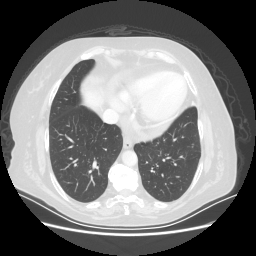

Original NATIVE CT scan (input)

Lung window (WL -600, WW 1500 β†’ Low βˆ’1350, High +150)

Reconstructed NATIVE CT scan (cycle consistency)

Original VENOUS CT scan

Generated VENOUS CT scan (A→B translation)